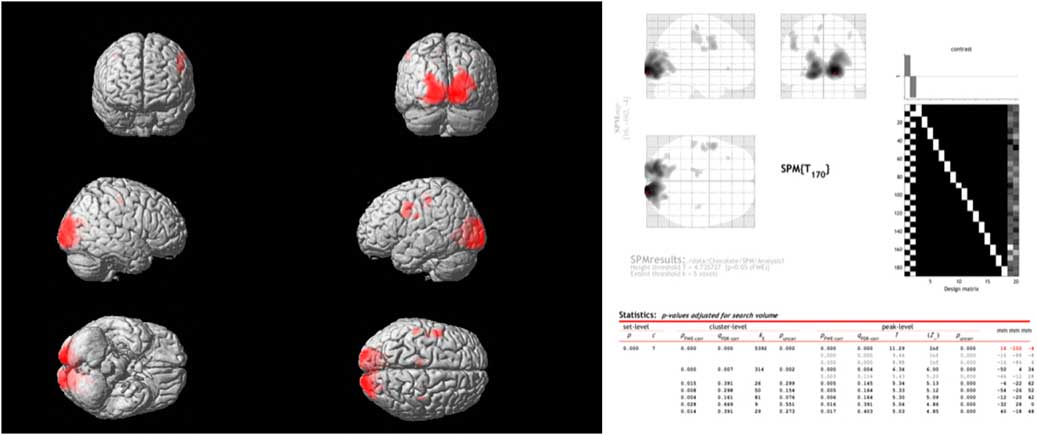

Comparing the spontaneous steady-state cerebral glucose metabolism of dark chocolate intake v. white chocolate, the PET–CT imaging showed a highly significant increase in regional glucose metabolism in a large cluster of voxels in the occipital and visual cortex as well as in more circumscribed clusters located in the somatosensory cortex, motor and pre-frontal cortices (Fig. 3). All voxel clusters showed highly significant effects both on the level of cluster and peak intensity analysis (both P<0·001, corrected for multiple comparisons).

Fig. 3 Combined positron emission tomography (PET)–computed tomography data (left panel) reconstructed to generate an image of relative glucose metabolism. Ingestion of dark chocolate with high cocoa content increases [18F]fluorodeoxyglucose uptake in the visual cortex, with increased activity also in areas of the somatosensory cortex (possibly involved in gustation), motor and pre-frontal cortices (both P<0·001). Averaged PET data with detailed results (right panel) highlight the differences in brain activation after ingestion of dark and white chocolate.

Instead, PET–CT imaging revealed specific effects of dark chocolate on regional glucose metabolism within the occipital and visual cortex, with smaller areas of increased brain activity also in areas of the somatosensory cortex (possibly involved in gustation), motor and pre-frontal cortices (Fig. 3). This result is unlikely to be due to ‘visual exposure’ to the different test meals. Although the radioactive marker (FDG) was injected during ingestion of the white and dark chocolate mousse, measurements commenced only after completion of the meal and were obtained in a closed scanner with little visual stimulation. It is more likely that biologically active substances present in cocoa had effects on regional brain activity. Flavanols have effects on vascular endothelium that increase peripheral, cardiac and cerebral blood flow via dose-dependent increases in flow-mediated vasodilation( Reference Schroeter, Heiss and Balzer 35 , Reference Sorond, Lipsitz and Hollenberg 36 ). Controlled studies performed by experimental psychologists indicate consumption of high-dose cocoa flavanols (250–1000 mg) improves a variety of cognitive tasks, including visual contrast sensitivity, time to detect motion direction and spatial working memory performance( Reference Scholey, French and Morris 37 – Reference Karabay, Saija and Field 39 ). Since increased delivery of substrates improves the performance of mentally effortful tasks, the findings of the PET–CT study may indicate that improved performance of visual information processing is related to effects of cocoa flavanols on the perfusion and regional metabolism of the visual cortex and other higher centres. It is less likely that the results are mediated by methylxanthines in dark chocolate. Caffeine and to a lesser extent theobromine increase alertness, especially in subjects with fatigue, and this is associated with activity in regions involved in the control of vigilance, anxiety and cardiovascular regulation( Reference Scholey and Owen 12 , Reference Boekema, Samsom and van Berge Henegouwen 31 ); however, these substances do not have established effects on the areas identified in this study.